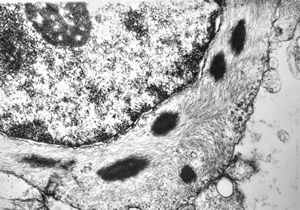

phagocytosed Nocardia (Actinomycetales) … cerebellar absces